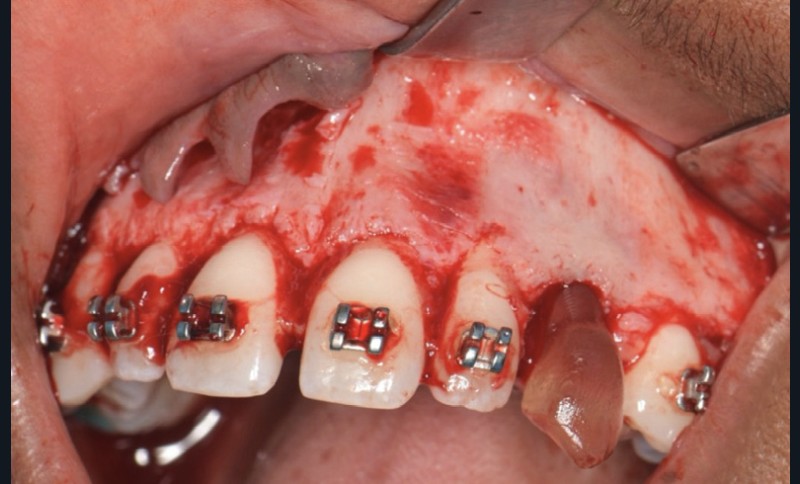

Une fois l’espace nécessaire obtenu, des cales molaires sont réalisées pour limiter les interférences occlusales avec la 23. La 63 et l’odontome sont extraits (fig. 4). Un lambeau est levé et la réplique 3D de la 23 est essayée dans l’alvéole, qui est adaptée en fonction (fig. 5). La 23 est prélevée de façon atraumatique (fig. 6) et auto-transplantée (fig. 7). Après suture du lambeau (fig. 8), une contention par arc acier 0,019×0,025’’ avec un CVI entre la dent et l’arc orthodontique est réalisée (fig. 9). Trois ou quatre semaines après l’auto-transplantation (fig. 10), le traitement endodontique est effectué (fig. 11). Un bracket orthodontique pourra être collé de façon passive, et la dent prise en charge avec un arc Niti 0,017 x 0,025’’ (fig. 12).